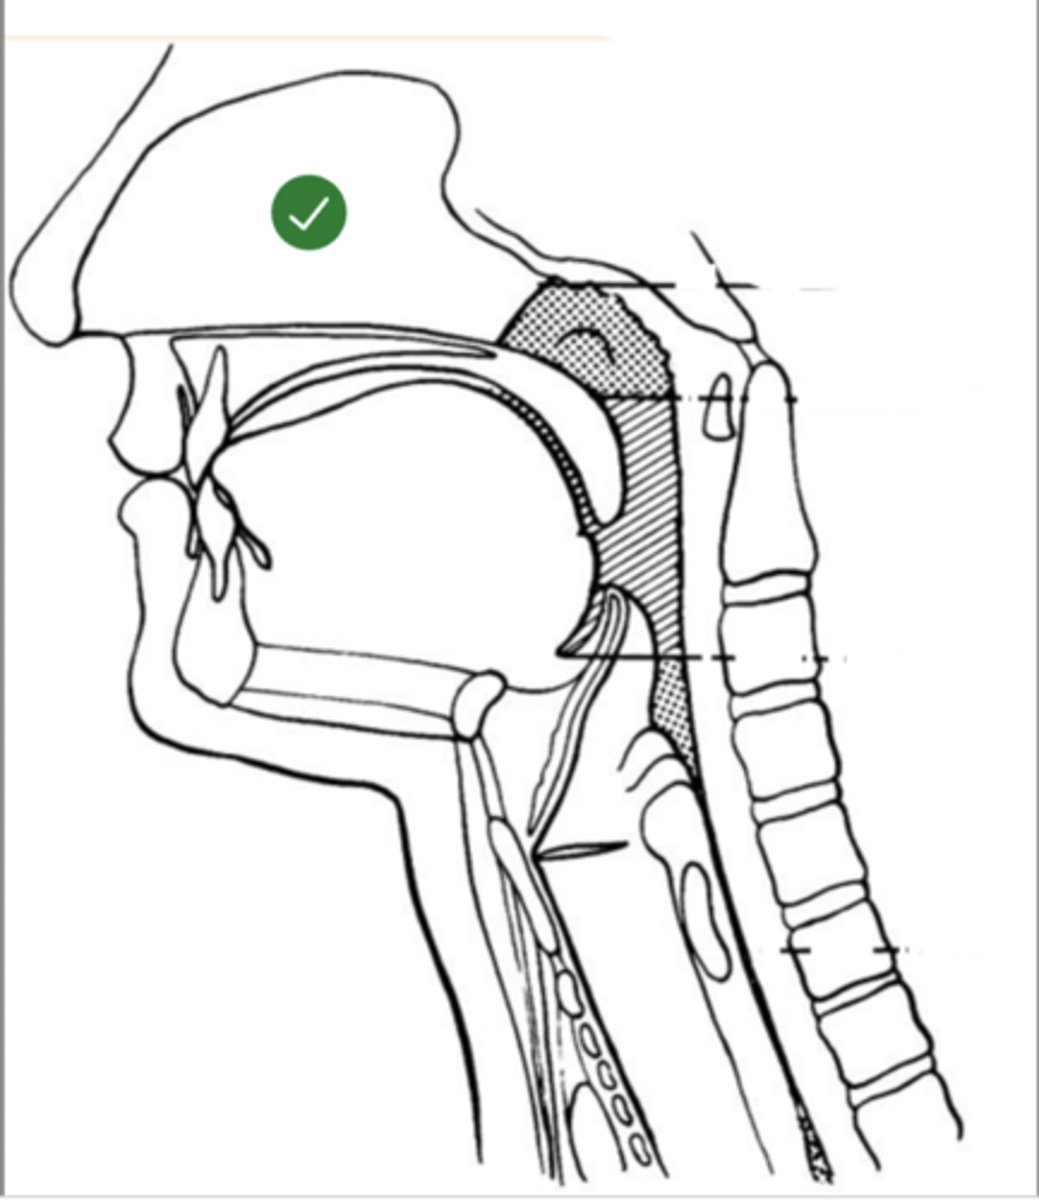

Label base of tongue (lateral view)

label anterior tongue (lateral view)

Label posterior/ back of tongue (lateral view)

Label Mandible (lateral view)

Label velum/ soft palate (lateral view)

Label hyoid bone (lateral view)

Label epiglottis (lateral view)

Label thyroid cartilage (lateral view)

Label posterior cricoid (lateral view)

Label trachea (lateral view)

Label upper esophageal sphincter (lateral view)

Label esophagus (lateral view)

Label posterior pharyngeal wall (lateral view)